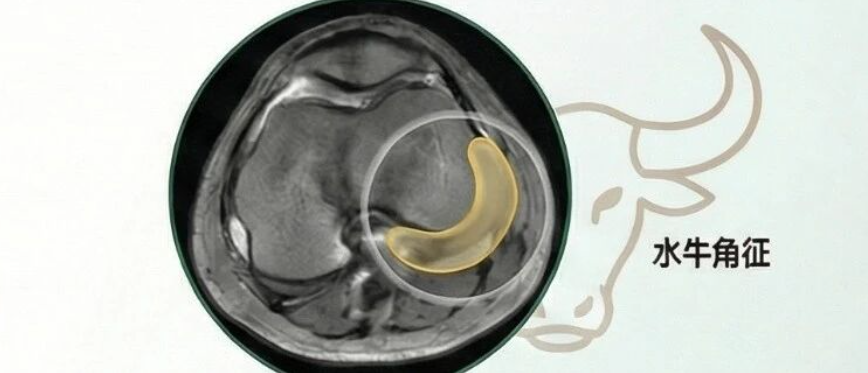

人工膝关节置换基本技术

30分钟

3.1万人学习